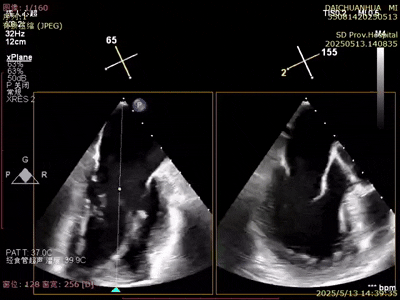

術(shù)后超聲

反流變?yōu)檩p度,反流等級(jí)從4+降為1+;

術(shù)后平均跨瓣壓差1mmHg;

夾子夾合量:前葉15mm,后葉10mm;

剩余瓣環(huán)面積:術(shù)后有效瓣環(huán)面積3.7cm²;

二尖瓣3區(qū)可見(jiàn)夾子強(qiáng)回聲,位置固定。